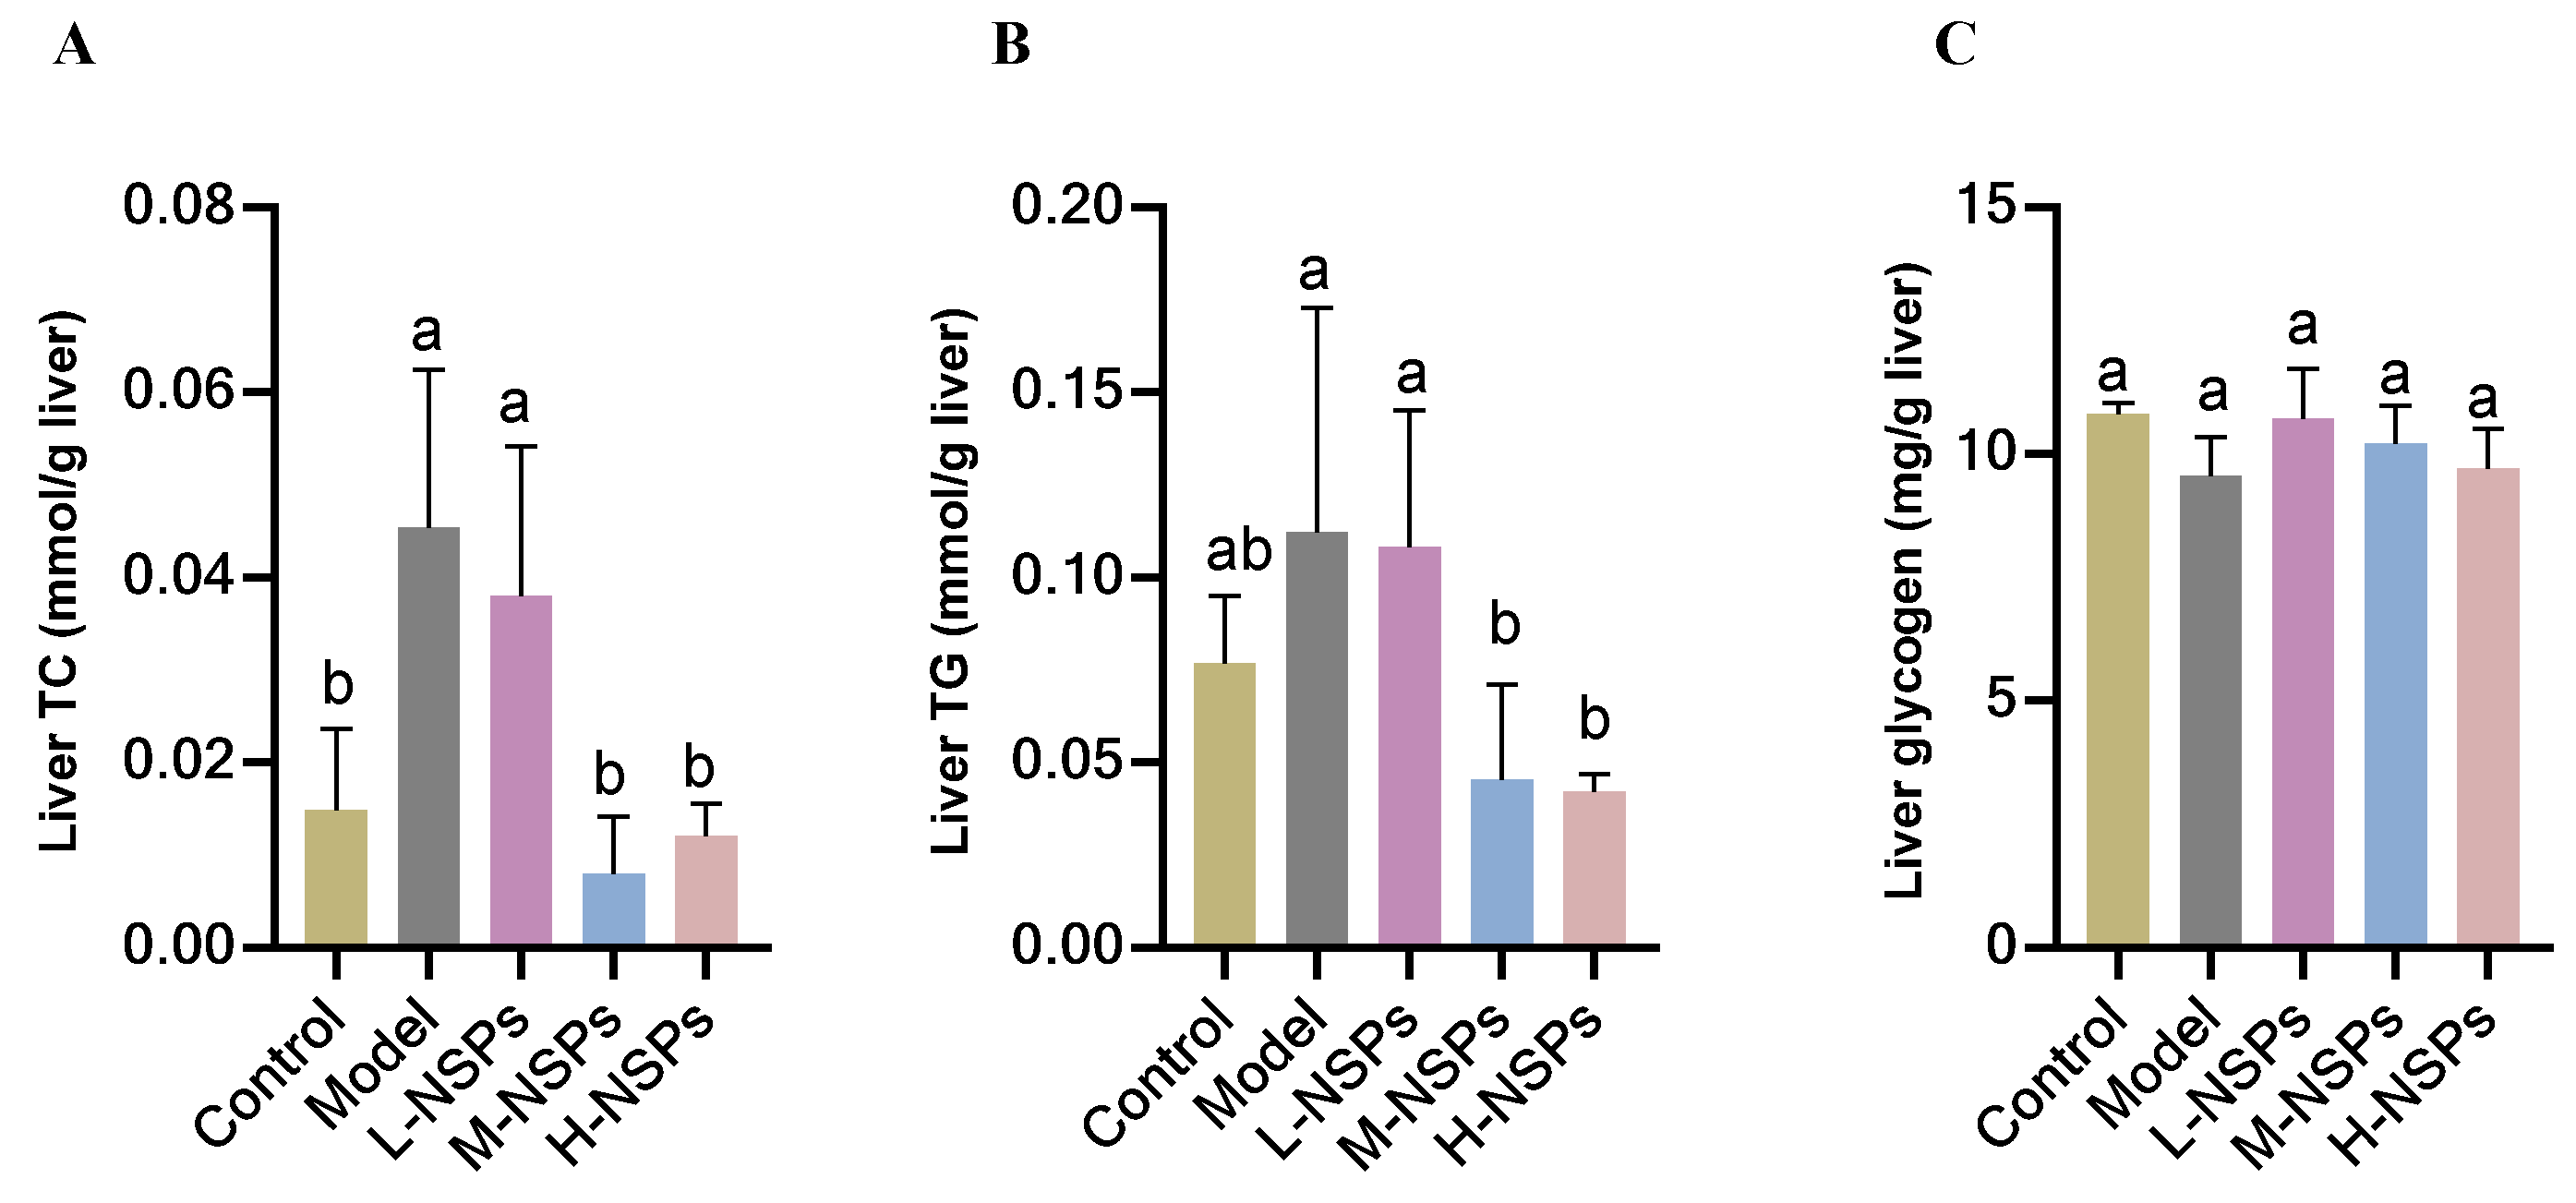

3.13. The Effect of NSPs on Liver Lipid Accumulation of Diabetic Mice

3.14. The Effect of NSPs on Liver Glycogen Content of Diabetic Mice